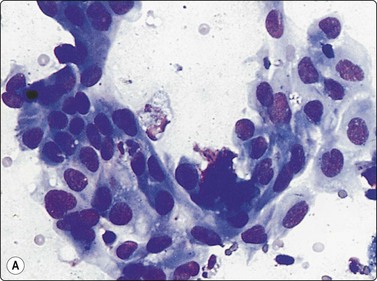

image image

Fig. 8.18 Adenocarcinoma, well differentiated

(A) Monolayered sheets and papillaroid clusters of glandular cells (H&E, HP); (B) 3-D clusters and a sheet of glandular cells with a palisaded edge (H&E, HP). Diagnosis of malignancy based on abundance of material and complex architecture.

Fig. 8.19 Adenocarcinoma

(A) Monolayered sheet of glandular cells showing enlarged hyperchromatic nuclei with irregular outlines and several intranuclear cytoplasmic inclusions (H&E, HP). (B) 3-D clusters of glandular cells (MGG, HP). Inset: intranuclear cytoplasmic inclusions (MGG, HP oil).